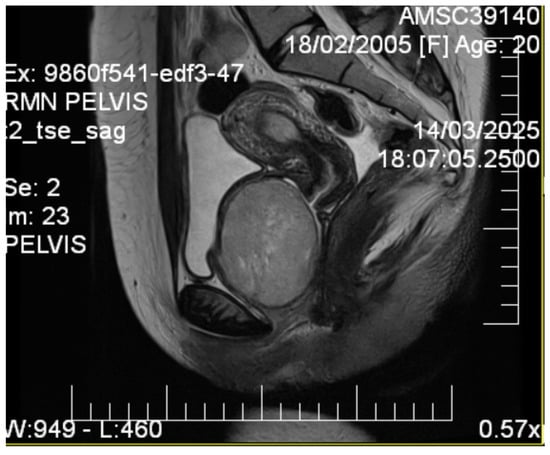

Initial transvaginal ultrasonography revealed a well-circumscribed, solid, predominantly hypoechoic mass measuring (6.9 × 6.5) cm located in the vesicovaginal region (Figure 1). The mass demonstrated homogeneous echotexture with well-defined borders and no internal cystic components. Color Doppler evaluation showed minimal internal vascularity. The uterus measured within normal limits, but demonstrated a fundal contour abnormality suggestive of septate uterus. Both ovaries appeared normal.

Additional abdominal ultrasonography confirmed a well-circumscribed mass measuring 6.07 × 6.10 cm from alternative imaging planes, demonstrating consistency with initial findings (Figure 2).

Figure 2.

Abdominal ultrasonographic image visualizing the well-demarcated, solid, hypoechoic mass (calipers) in the vesicovaginal region measuring (6.07 × 6.10) cm, confirming a consistent solid nature.